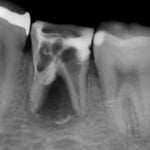

他院で抜歯と診断された症例です。友人の歯科医師の紹介で遠方から通院されました。初診時(左図)には、楔印で示すように、歯の根の先に黒い影が明瞭に写っています。が治療開始から8ケ月後(右図)では、黒い影は消えたり縮小しています。

歯の根の先の黒い影も消え(左図)、(手前は完全に消えていないが、完全な縮小傾向と症状がない)たので、クラウンを装着するための型採りをします。

右図の楔印は破折線です。破折線は特殊な方法で修復しています。